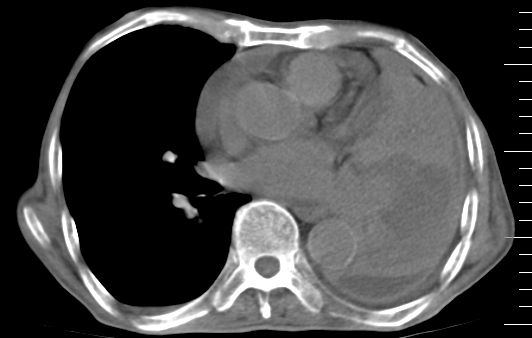

标题: CT10141:男、84岁,咳嗽、咯血1年。 [打印本页]

标题: CT10141:男、84岁,咳嗽、咯血1年。

支持左侧中央型肺癌伴下叶肺不张\\纵隔淋巴结转移.左侧包裹性胸腔积液\\心包积液.左侧少量胸腔积液..慢性支气管炎伴部分间质纤维化.

咯血病史较长,左肺下叶实变,体积未明显缩小,隐约可见血管影及坏死阴影,双肺门及纵隔淋巴结增大,心包增厚积液,纵隔右移位,单侧胸腔积液,首先考虑:大叶型肺泡癌伴纵隔心包转移。